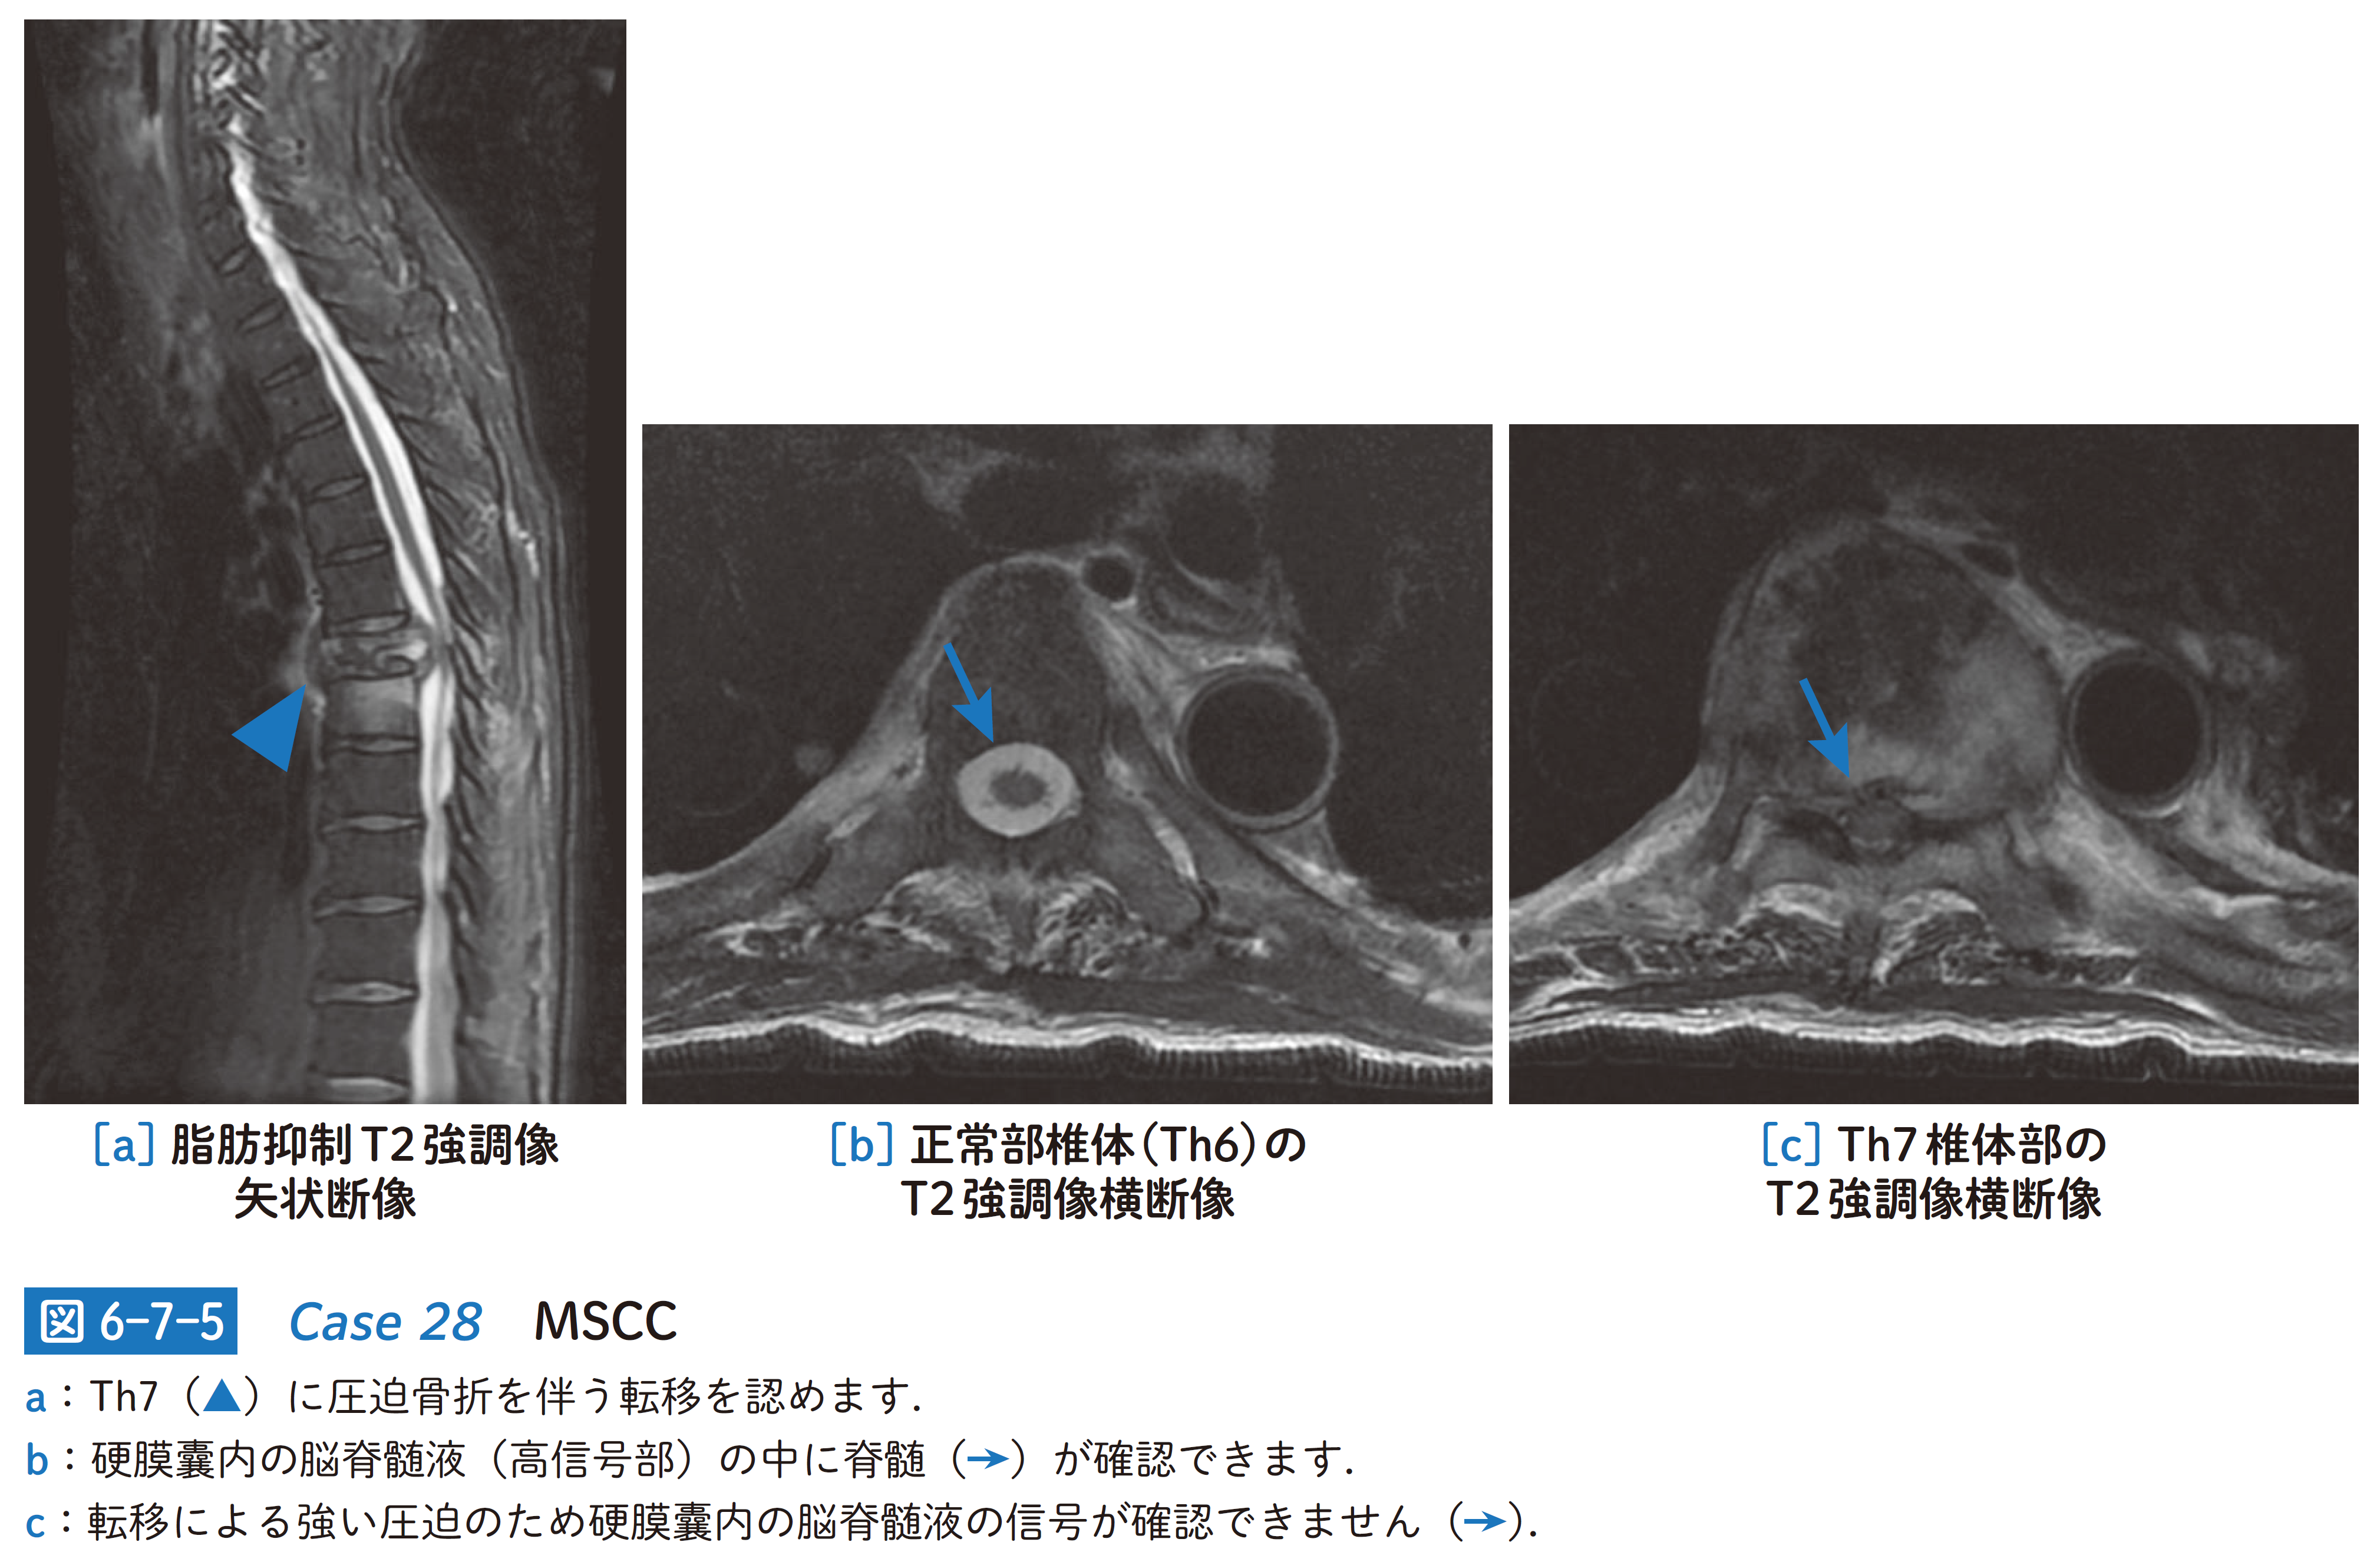

1. 画像の見方(図6-7-5)

□Th7椎体骨に圧迫骨折を伴う転移を認め,同部にはT2強調像で高信号変化が広がっています(図6-7-5a).圧迫骨折により椎体後方から飛び出した腫瘤は硬膜嚢内の脊髄を強く圧排(→p48)しています.

□硬膜嚢内は通常,脳脊髄液(T2強調像で高信号)で満たされていますが( 図6-7-5b),腫瘍により強い圧排を受けた病変部レベルの硬膜嚢内には脳脊髄液の信号が確認できません( 図6-7-5c).

□神経根や脊髄圧迫による神経症状を伴うMSCCと診断されました.圧迫骨折を併発しており,不安定性の観点からも早急の処置を要する病態です.